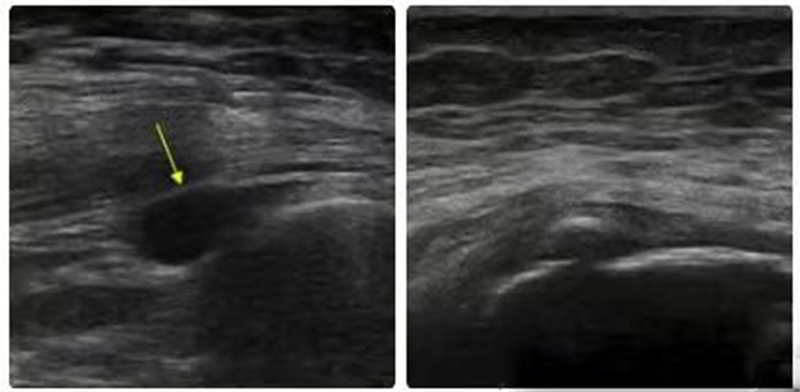

超声检查具有较好的可耐受性、可行性、价格低廉、纤维和血管分布的空间分辨率高等优点,超声检查显示大转子滑囊无回声或低回声液体则提示转子滑囊炎。肌腱的撕裂显示增厚的低回声肌腱伴纤维的连续性中断或者无回声,以及肌腱的钙化。多普勒超声检查可以测量肌腱的厚度和血管的分布。超声检查还可以发现骨侵蚀、肌腱病变和髂胫束增厚等。